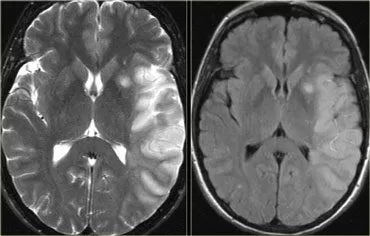

شكل جلطة المخ في الرنين المغناطيسي

جلطة المخ قد تظهر بأشكال مختلفة على الرنين المغناطيسي (MRI) وذلك بحسب نوع الجلطة وتأثيرها على الأنسجة المخية. يمكن أن تظهر بصور مختلفة باعتماد على الزمن والمكان والتغييرات في الأنسجة المخية المحيطة. إليك وصفًا عامًا لأشكال ممكنة لجلطة المخ في الرنين المغناطيسي:

1. الجلطة الإفقارية (Ischemic Stroke) في الرنين المغناطيسي:

في الرنين المغناطيسي، شكل جلطة المخ الإفقارية قد تظهر عادة على الصور بشكل منطقة مظلمة في تصوير T1-weighted ومظهر أكثر سطوعًا في تصوير T2-weighted. قد تظهر أيضًا تعزيزات (توهجات) بيضاء في صور ما بعد الحقن بمادة الصبغة على حدود الجلطة المخية.

2. الجلطة النزفية (Hemorrhagic Stroke) في الرنين المغناطيسي:

في حالة جلطة المخ النزفية، سيظهر الدم عادة على الصور بلون أبيض أو فاتح. يمكن أن يكون للمنطقة المصابة شكل غير منتظم وبملمس مشابه للسائل، وقد يكون للدم تأثير كبير على تباين الصور المتعلق بالدم والأنسجة المحيطة.

يجب ملاحظة أن الصور على الرنين المغناطيسي تعتمد على الأجهزة والتقنيات المستخدمة، وتقديم تشخيص دقيق يعتمد على تقييم الأطباء المتخصصين بالرنين المغناطيسي وفهمهم العميق للتشريح والتغييرات التي يمكن أن تحدث بسبب جلطة المخ.